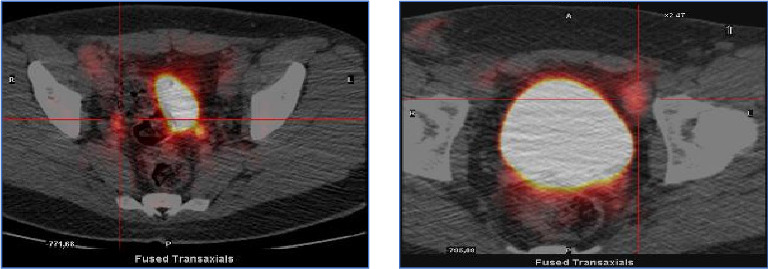

成人朗格汉斯细胞组织细胞增多症(LCH)是一种罕见的疾病。该病表现为局灶性或多灶性累及单一器官/系统或局灶性或弥散性多系统疾病。累及中枢神经系统(CNS)也不常见,尿崩症是垂体后叶病变的常见表现。活检证实诊断为特征性朗格汉斯细胞浸润,免疫组化S100蛋白、CD1a和CD68细胞阳性。患者表现为全身性淋巴结病,在淋巴结活检中被诊断为低风险单系统lch基础的独特病理表现。在疾病期间,记录了中枢神经系统受累,患者接受了不同的顺序治疗方案,实现了8年的完全缓解。在成年LCH患者中,随着淋巴结病和中枢神经系统病变的消失,缓解持续时间延长是一种不寻常的临床观察。

Langerhans cell histiocytosis (LCH) in adults is a rare condition. The disease presents with focal or multifocal involvement of a single organ/system or focal or disseminated multisystem disease. Involvement of the central nervous system (CNS) is also infrequent, with diabetes insipidus as a common manifestation of posterior pituitary lesions. Biopsy-proven diagnosis with the observation of characteristic Langerhans cells infiltrate with positive immunohistochemistry of S100 protein, CD1a, and CD68 cells. The patient presented generalized lymphadenopathy and was diagnosed with low-risk single-system LCH-based distinctive pathological findings in a lymph node biopsy. During the disease, CNS involvement was documented and the patient received different sequential therapeutic schemes, achieving complete remission that has been maintained for 8 years. The prolonged duration of remission with disappearance of lymphadenopathy and CNS lesions in an adult patient with LCH is an unusual clinical observation.